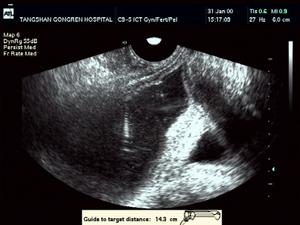

b型超聲可探及囊性腫物。造影后可通過導管直接把抗生素注入囊內,如無效,可行手術切除囊腫。精囊腺腫瘤更為少見,b型超聲檢查腫物為實性,精囊腺造影顯示腫瘤占據空間形成的造影劑充盈缺損,此時應手術切除腫物。

(10)精道造影多採用經皮穿刺輸精管精道造影,對精囊囊腫診斷有重要價值,可顯示囊腫的位置、形態、大小、是否合併精囊結石及精道有無狹窄。符合上述第(1)~(4)項可擬診,第(5)~(10)項對於囊腫的位置、形態、大小、數目的診斷有價值,確診需術中的病理證實。

症狀下腹部或腰部疼痛,會陰、睪丸或直腸等部位不適,尿頻、膿尿、排尿困難、血精及血尿等。直腸指診時可在前列腺側方捫及單發的、大小不等的囊性腫物,其邊緣光滑完整,質韌有彈性。囊腫液檢查精囊本身的囊腫其囊液內含有精子。精囊造影經同側輸精管逆行造影或經會陰直接穿刺造影可見精囊受壓充盈缺損及囊腫圓形陰影。